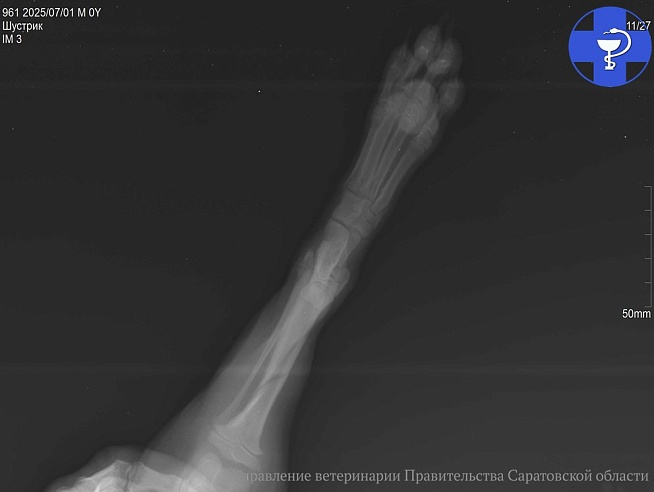

В ветеринарную лечебницу обратилась хозяйка щенка по кличке Шустрик. Женщина жаловалась на снижение активности питомца и хромоту на левую тазовую конечность. Специалисты осмотрели малыша и пришли к выводу, что у Шустрика косой оскольчатый перелом большеберцовой кости. Об этом корреспонденту телеканала "Саратов 24" рассказали в управлении ветеринарии по Саратовской области.

Шустрику назначили консультацию и осмотр травматолога для последующего проведения остеосинтеза кости.